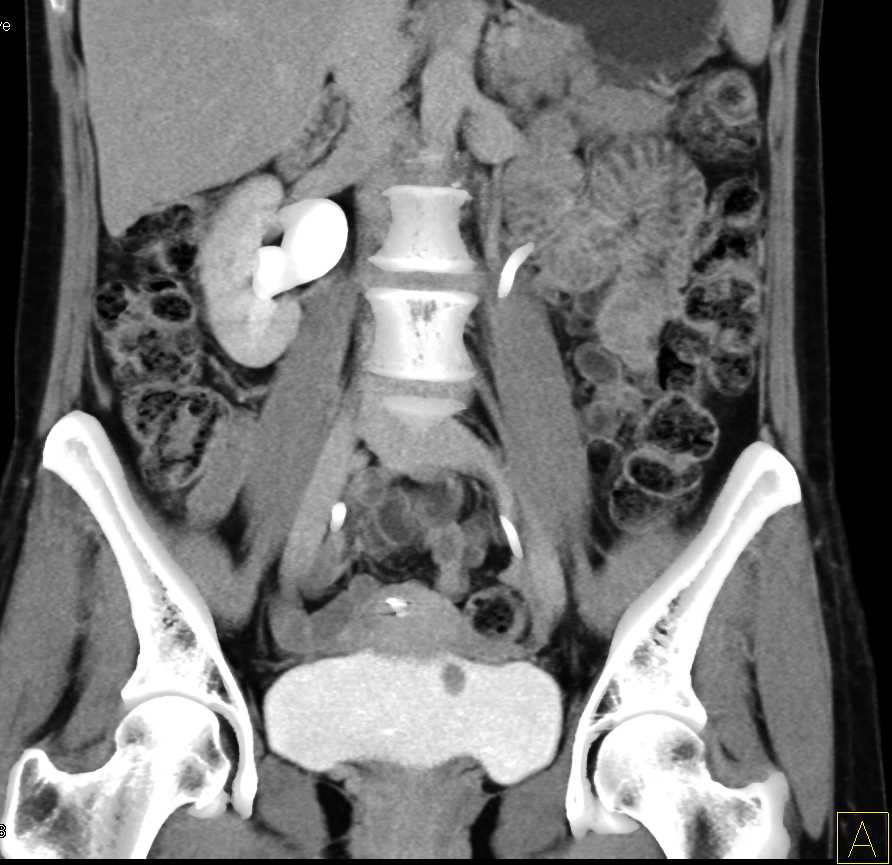

Bladder Cancer with Active Bleed